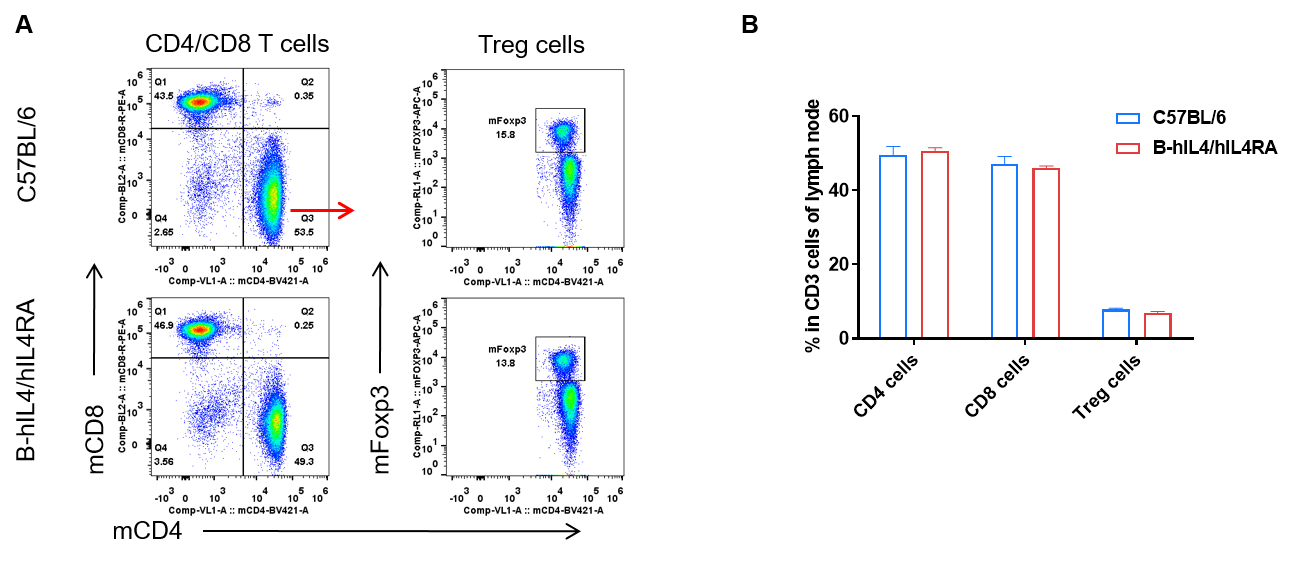

Analysis of subpopulation of T cells in lymph node by FACS. Lymph nodes were isolated from female C57BL/6 and B-hIL4/hIL4RA mice (n=3, 10-week-old). Flow cytometry analysis of the lymph nodes was performed to assess leukocyte subpopulations. A. Representative FACS plots. Single live CD45+ T cells were used for further analysis as indicated here. B. Results of FACS analysis. Percent of CD8, CD4, and Treg cells in homozygous B-hIL4/hIL4RA mice were similar to those in the C57BL/6 mice, demonstrating that introduction of hIL4 and hIL4RA in place of its mouse counterpart does not change the overall development, differentiation or distribution of these T cell subtypes in lymph node. Values are expressed as mean ± SEM.